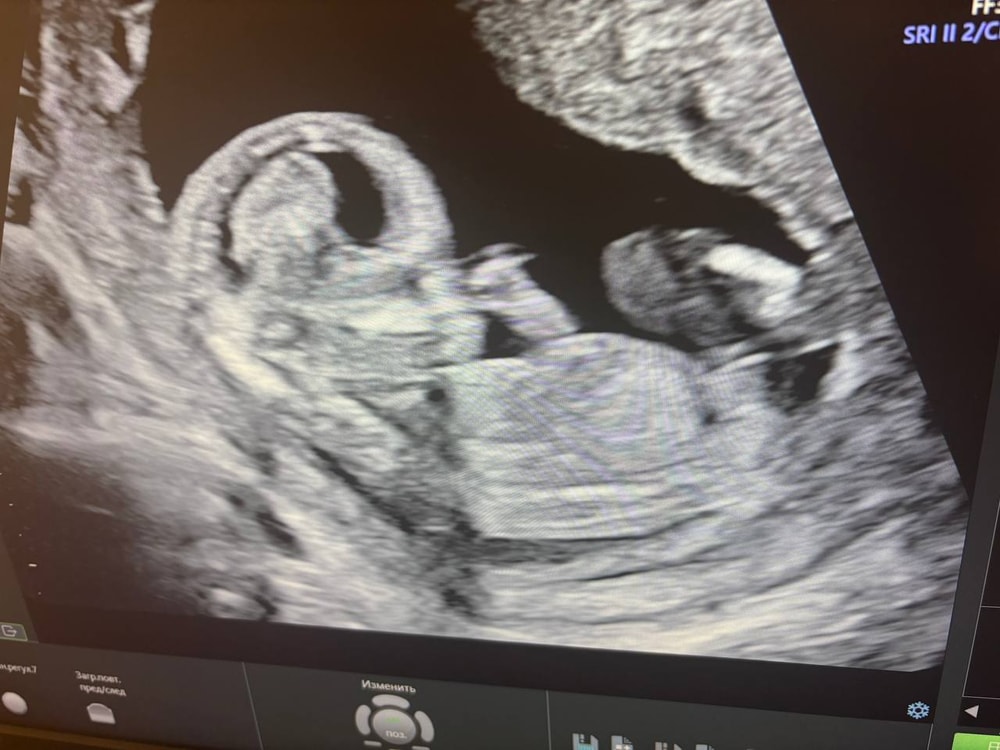

Девушки в регистратуре оказались очень милыми, все рассказали, да и в целом персонал мне понравился. Нам сказали, что от врача зависит разрешит ли мужу зайти тоже посмотреть и только в конце пускают. Немного расстроились изначально, но в итоге оказалось зря. Мне померили давление и потом отправили на УЗИ. Делали его мне около получаса, малыш показался во всей красе изначально. И так повернется, и сяк, и ручкой помашет и пальчики в рот положит (см. фото 1,2). Врач сказала, что малыш отлично развит для срока, все у него в норме, послушали сердечко, посчитали пальчики, похвалили наш профиль, сказали, что красивый))))) Зовут нашего папу тоже посмотреть и тут начинается самое интересное. Как только муж садится и начинаем смотреть, булочка, устав от внимания, демонстративно отворачивается и мы во всей красе лицезреем попку и спинку))) ну вот спасибо))) Врач уже и так, и так пыталась растормошить его, но максимум на что удалось его подбить, это посмотреть на нас через плечо, видимо с мысль "да отстаньте вы уже от меня" (см. фото 3). Но было прям очень забавно это, особенно учитывая тот факт, что это уже не первые его(ее) прятки с папой. То допплером при нем сердечко не могу найти, то сейчас вот спрятался.